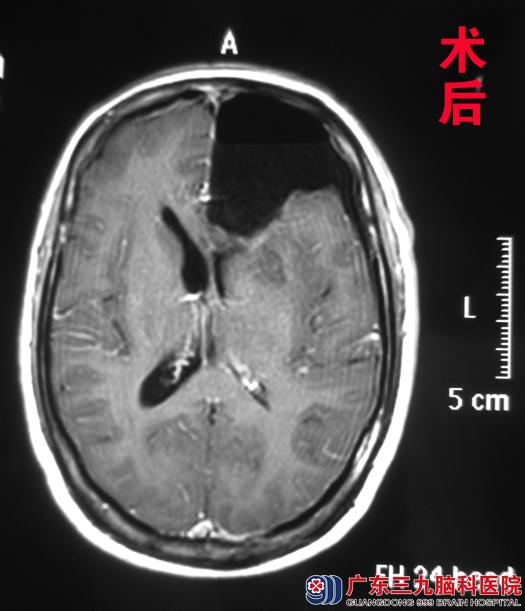

为求进一步治疗,黄女士经朋友介绍来到广东三九脑科医院综合神经外科(神经外五科)求治。入院头颅磁共振检查见:左侧额叶占位,大小约3.76 cm×5.55 cm×4.07cm。完善相关检查后,外五科鲁明主任主刀,在唤醒麻醉下为其行左侧额叶占位切除术+颅内压探头置入术。术中采用导航定位,用电生理探查术区皮层功能,术中显微镜下见白色肿瘤组织,血供一般,边界不清,在患者语言、运动配合正常下,全切肿瘤,手术顺利结束。术后黄女士未出现语言及肢体功能障碍,顺利康复。术后病理结果:少突胶质细胞瘤(WHO II级)。